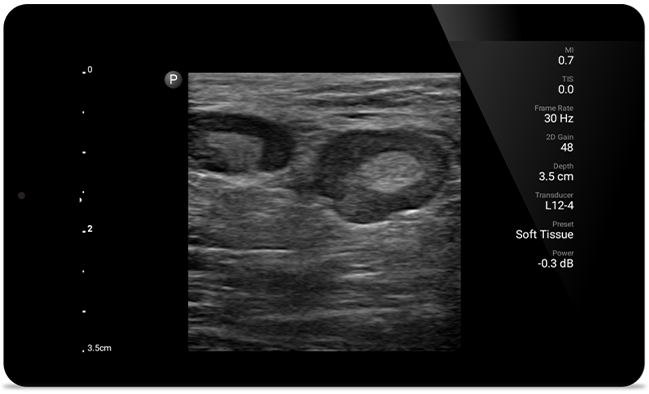

Get the clarity of larger ultrasound systems with Lumify

SonoCT reinforces real tissue imaging while eliminating random artifacts. This technology produces images superior to conventional imaging in up to 94% of patients.

• 5 to 2 MHz extended operating frequency range • 50mm radius of curvature • 2D, color Doppler, M-mode, advanced XRES and multivariate harmonic imaging, SonoCT • High-resolution imaging for deeper applications: abdominal, gall bladder, OB/GYN and lung imaging preset optimizations